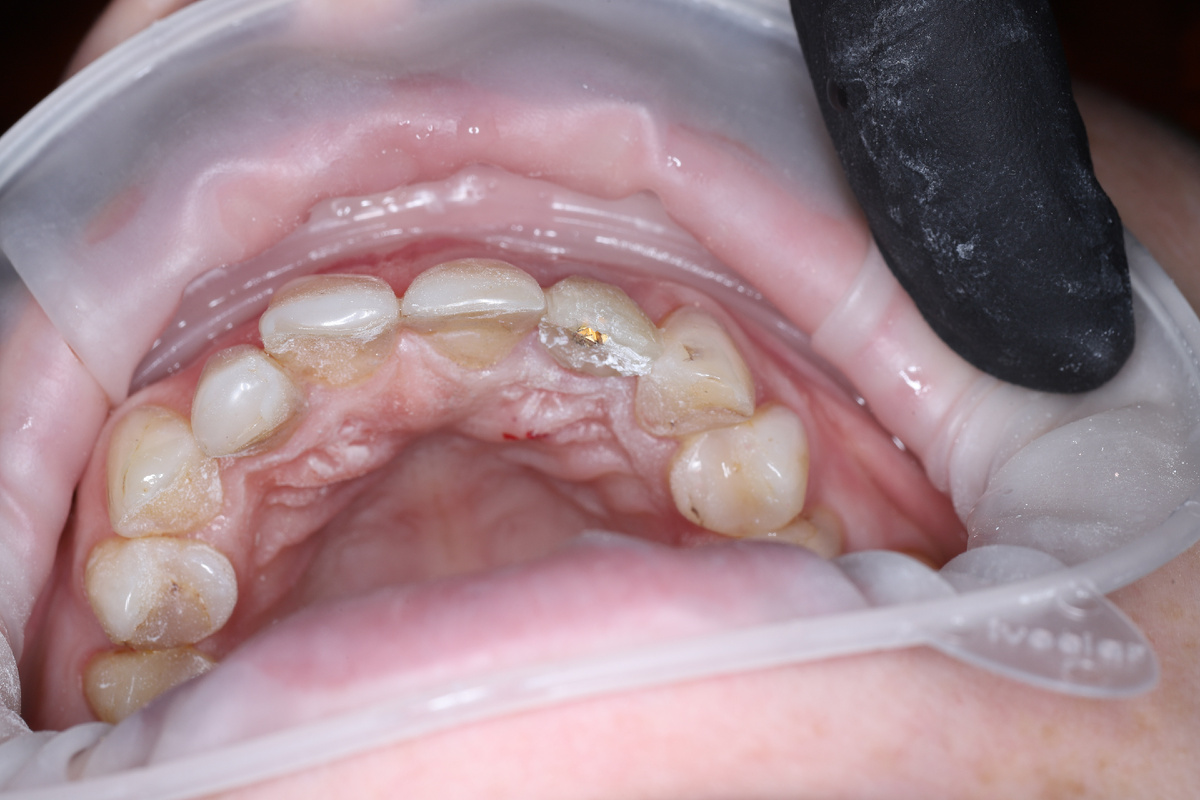

Ситуация до:

Я сделал наращивание на анкерном штифте пломбировочным материалом (смоделировал имитацию-прототип зуба), для того, чтобы сделать по этому макету временную коронку на импланте:

Снял слепок.